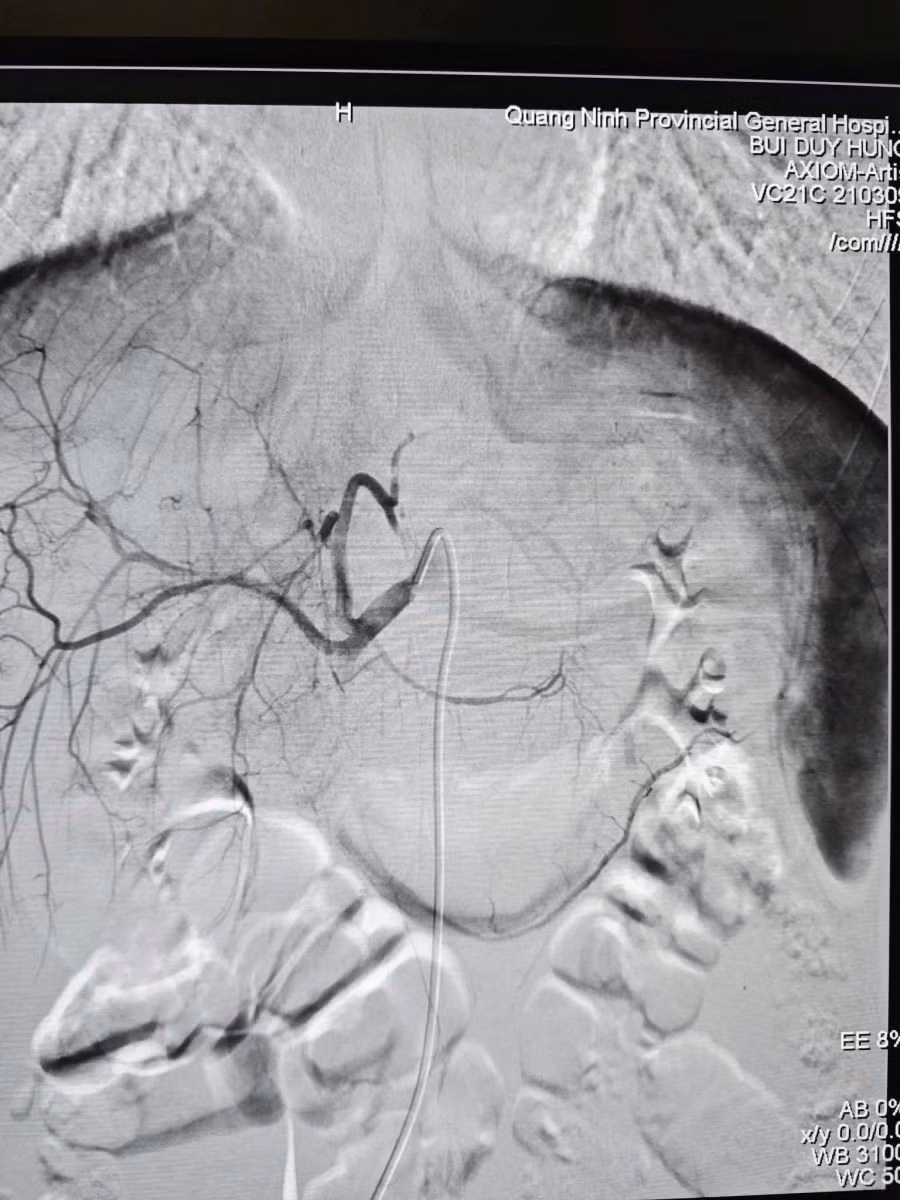

Hình tổn thương trên phim chụp DSA - Ảnh BVCC

Dưới sự hỗ trợ của hệ thống DSA hiện đại, ê-kíp đã luồn ống thông siêu nhỏ 1.9F tiếp cận siêu chọn lọc vị trí nhánh động mạch gan đang chảy máu và nút tắc.

Dưới sự hỗ trợ của hệ thống DSA hiện đại, ê-kíp bác sĩ đã luồn ống thông (Microcatheter) siêu nhỏ 1.9F tiếp cận siêu chọn lọc vị trí nhánh động mạch gan đang chảy máu và nút tắc bằng vật liệu chuyên dụng Spongel.

Ê - kíp can thiệp mạch do BSCKII Bùi Duy Hưng - Phó khoa Chẩn đoán hình ảnh – Điện quang can thiệp trực tiếp thực hiện